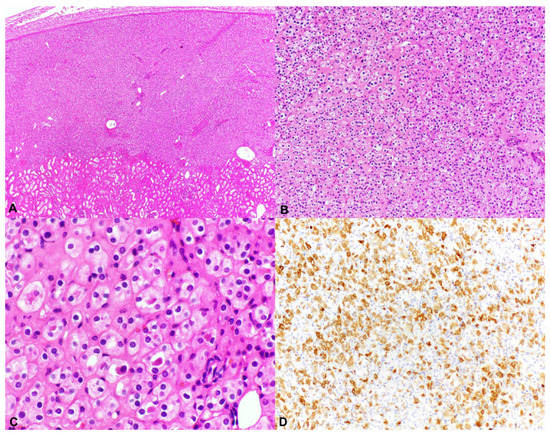

2.2. Hybrid Oncocytic/Chromophobe Tumor (HOCT); Chromophobe-Like RCC

2.3. Unclassified Renal Cell Carcinoma (Unclassified RCC); Granular Eosinophilic Macrocystic RCC